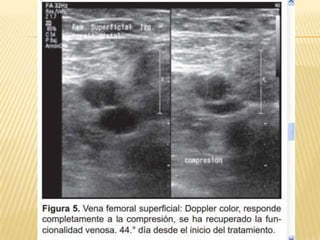

EVOLUCIÓN ECOGRÁFICA DE LA TROMBOSIS

VENOSA PROFUNDA EN PACIENTES CON

TROMBÓLISIS FARMACOLÓGICA

   Centro Médico ABC. The American British

Cowdray Medical Center IAP

   Anales de Radiología México 2010;2:76-

79. artíCulo original. Dr. José de Jesús

Rosas Sánchez, Dr. Miguel Ángel Ríos

Nava.